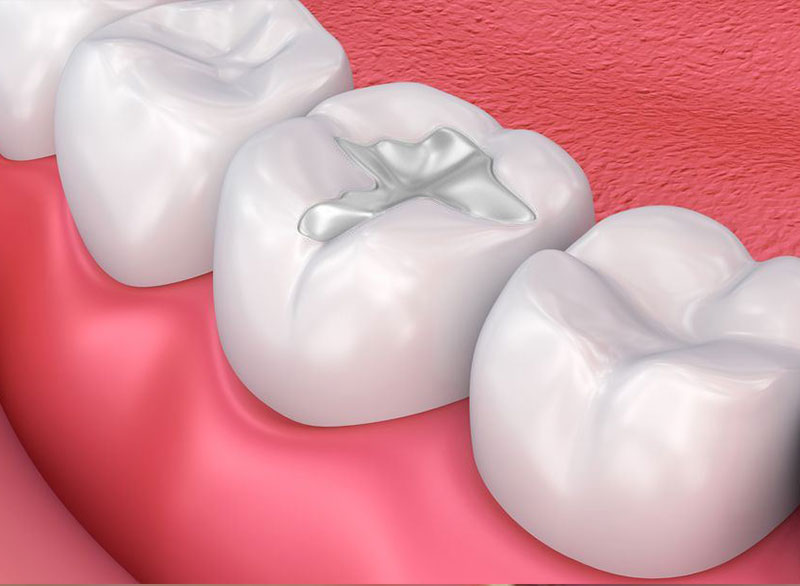

Resotration of a tooth/ teeth, using composite or amalgam material to prevent further decay.